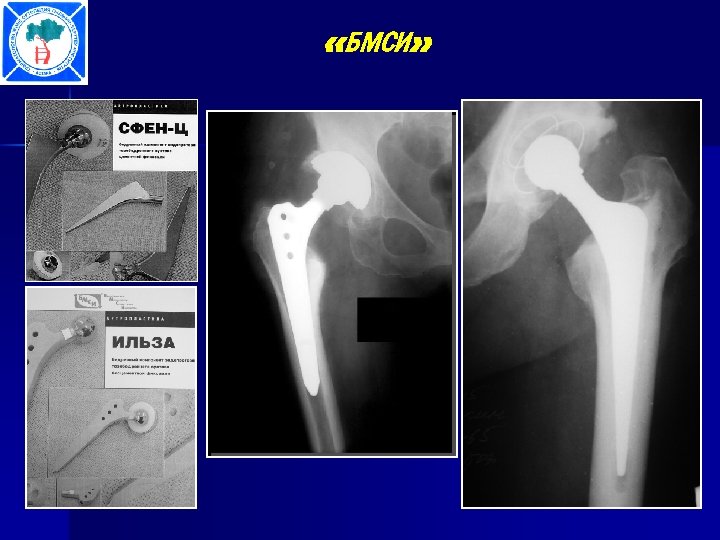

«БМСИ»

Больной Ж. , 48 лет:

Больной Ж. , 48 лет: Походка через 10 дней после операции